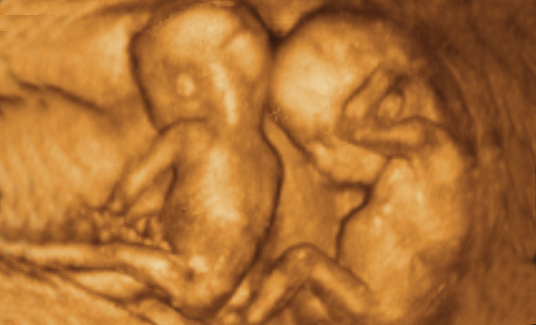

为宝宝留下成长的足迹是每一个准爸妈都想做的事情,准爸妈总是好奇宝宝在肚子里的动态,为了满足准爸妈的好奇心,安徽安琪儿妇产医院引进美国GE—E8四维彩超技术,该技术是目前国际上最先进的四维彩超技术,高清动态的显示胎儿的身体、骨骼、器官的发育情况,并通过高科技技术将宝宝的四维彩超影像刻成光盘,真正的实现零岁动态写真,可供准爸妈随时、反复的观看,为宝宝留下最珍贵的时刻。

四维彩超是目前最先进的一种彩超技术,准妈妈可以清楚的观看到宝宝的动态图像。医生也能够根据四维彩超图了解宝宝的发育情况,是否有唇裂、脑积水、畸形等异常情况,方便医生和孕妇及早的采取应对措施;根据胎儿现今的发育情况及时补充营养,更有助于宝宝的身体发育和智力发育,提高宝宝的健康指数。